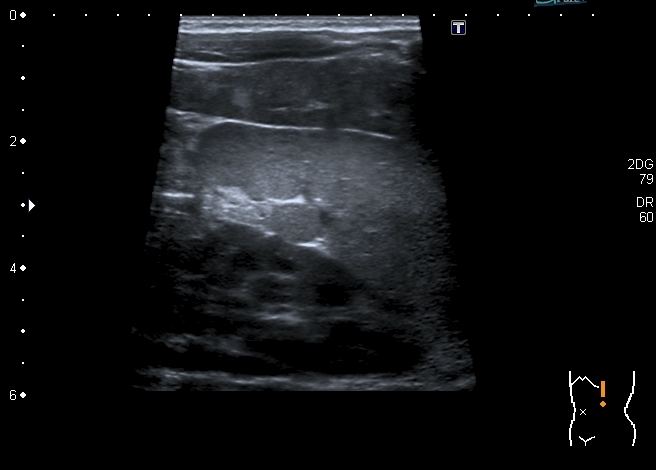

Правый надпочечник представлен округлым гиперэхогенным тканевым образованием с участками кальцификации, гиповаскулярным по отношению к ткани печени и почки

Моё заключение: нейробластома правого надпочечника с тотальным метастатическим поражением печени. Прошу членов форума высказать своё мнение о случае. Постараюсь отследить верификацию.

Верифицированный морфологически диагноз: С74.9 Низкодифференцированная нейробластома правого надпочечника с метастатическим поражением печени и костного мозга. T2N0M1, IVS стадия.